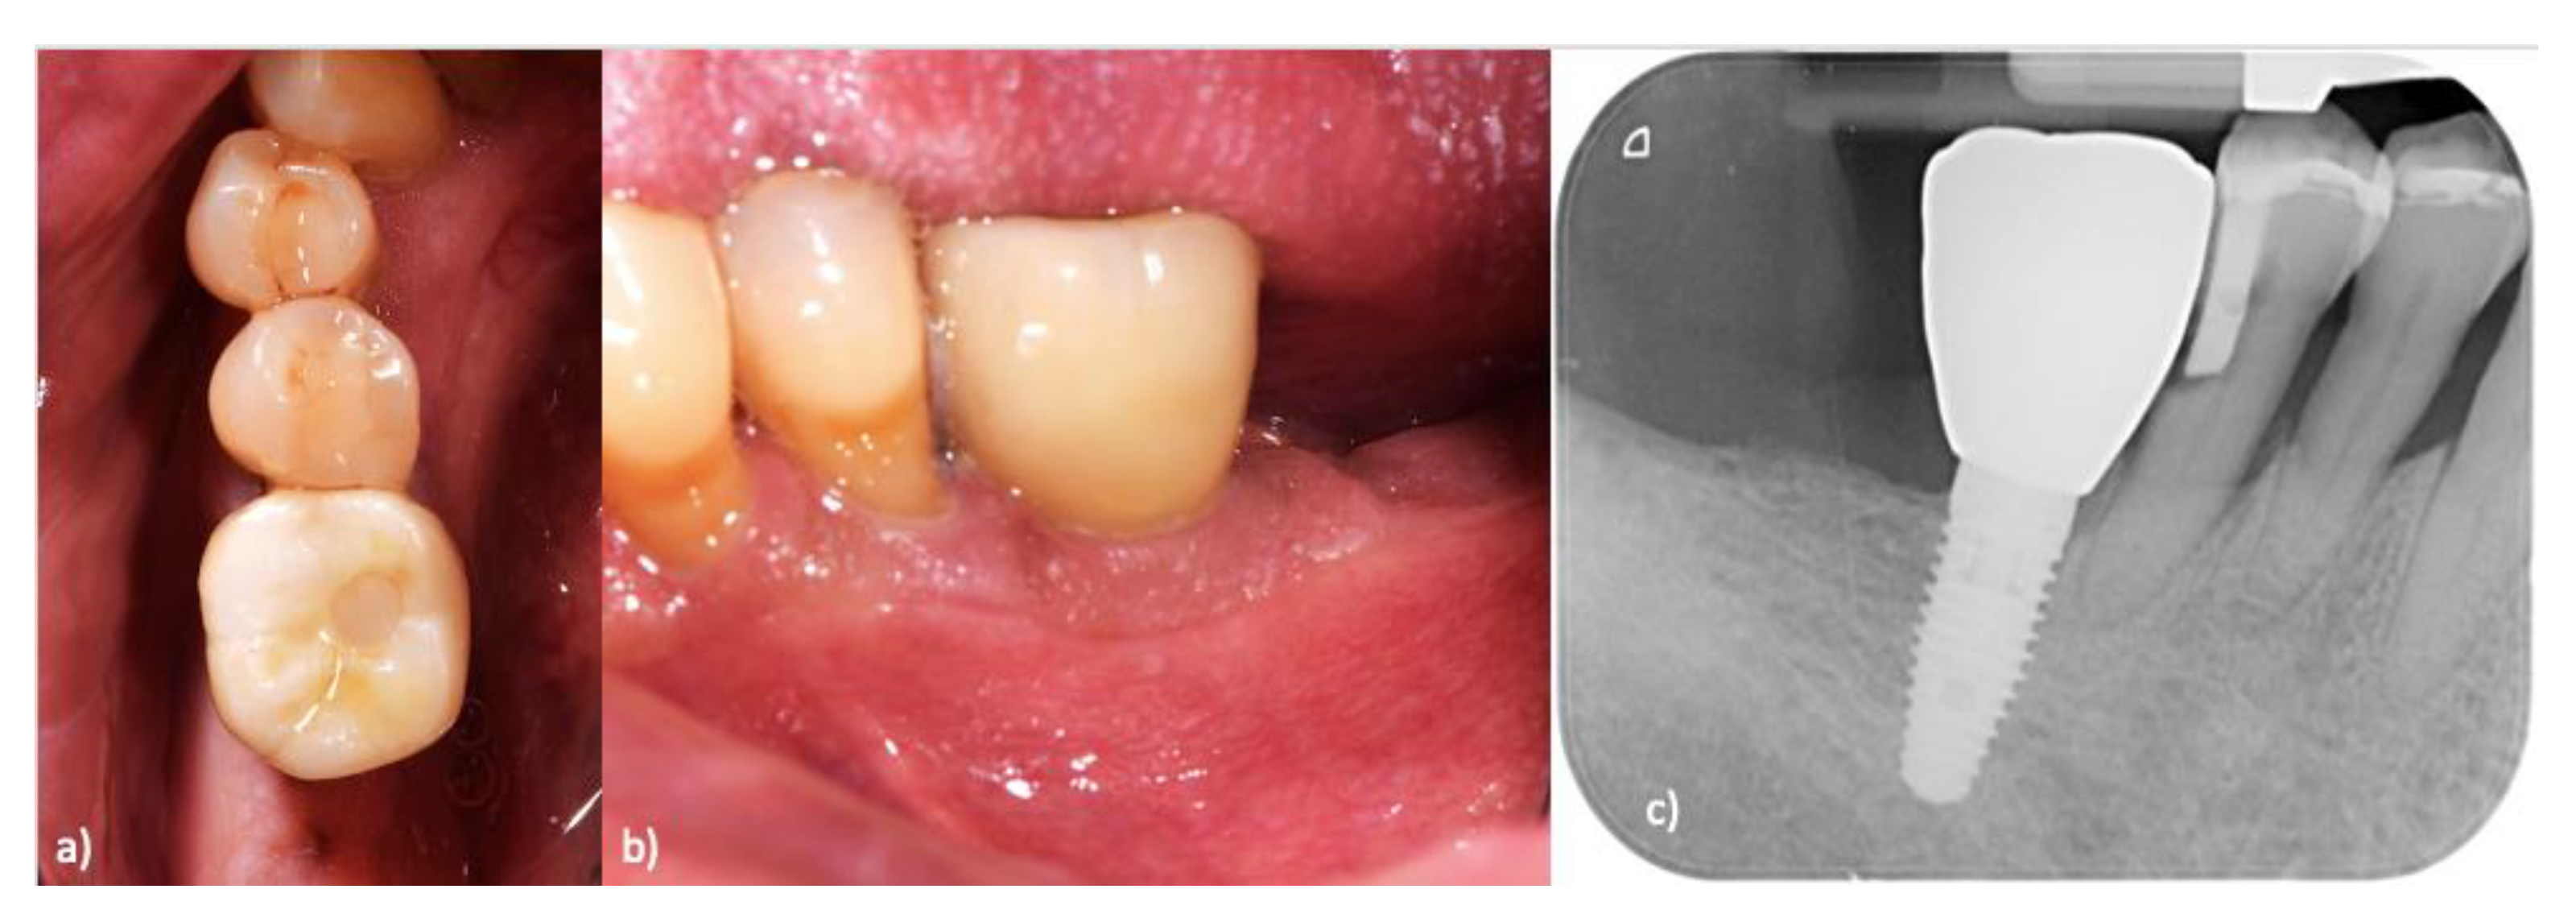

Clinical case (Figure 4).

Figure 4. Single-crown monolithic zirconia, screwed-on implant, for replacement of a missing first inferior molar: (a) occlusal view; (b) lateral view; (c) radiological appearance after 7 years.